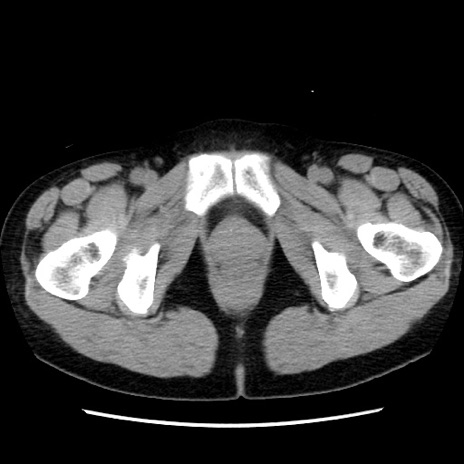

症例10(横断像)

【症例】 50歳代女性

【主訴】 腹痛

【現病歴】前日生レバーを食べた。今朝に排便あり。 昼前に突然発症の腹痛を生じ、当院救急外来を受診した。

【既往歴】 子宮筋腫にてで子宮全摘後

【身体所見】 意識清明、腹部:平坦、軟、下腹部やや左を中心に圧痛・反跳痛あり、筋性防御あり

【データ】WBC 7800、CRP 0.07